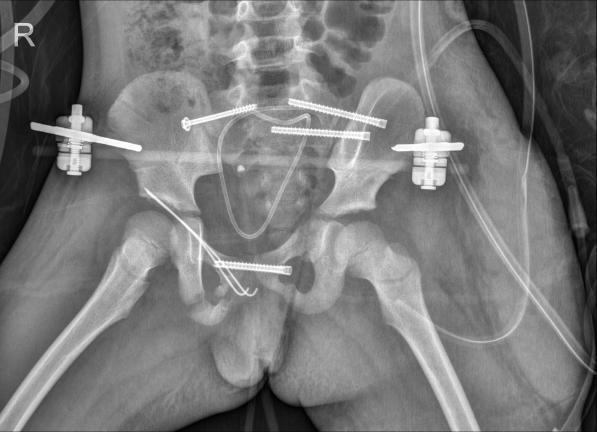

医生们仔细清理骨折部位间嵌插的软组织及凝血块,复位骨折部位,再用克氏针、空心钉等进行固定。为了保证治疗效果,他们还借助机器人导航技术,通过C形臂透视规划进钉位置和方向,在左右髋部外侧精准置入导针和空心螺钉。

樊仕才完成骨折内固定后,妇产科主任王雪峰上台为小花进行生殖道修复,细细缝合每一处裂伤和离断;紧接着,泌尿外科副主任医师罗新贵接力,为小花进行尿道修复。妇产科和泌尿外科的修复工作顺利完成后,樊仕才团队再次回到手术台,给小花置入外固定架固定针,连接外固定架,稳固骨折部位。

手术持续了7个多小时,最终顺利完成。术中小花失血约700毫升,通过及时输注4个单位红细胞悬液和400毫升新鲜冰冻血浆,小花的生命体征保持平稳,术后被安全送回病房。

术后